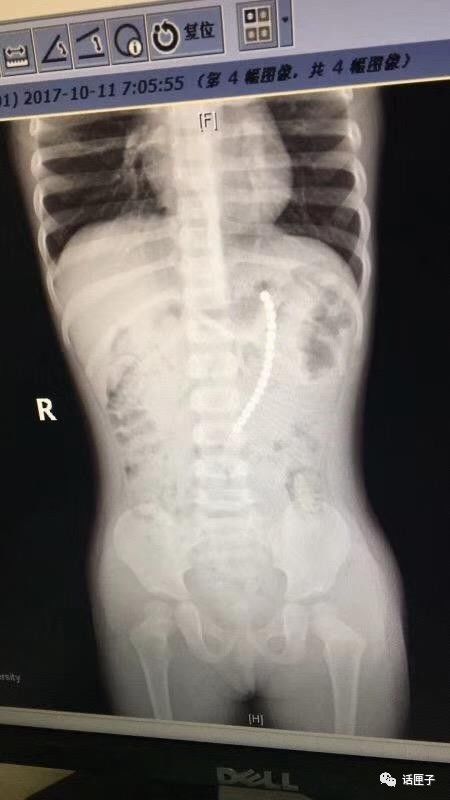

本市一户二宝家庭,父母给7岁的老大购买了一套巴克球,两岁的老二一直看着哥哥玩。几天前晚上,奶奶突然发现二宝正把一颗巴克球往嘴巴里放,还说喉咙里不舒服。奶奶一听,吓坏了!担心孩子把巴克球吞到了肚子里,赶快送医。复旦大学附属儿科医院医生给这个小女娃拍了片子,结果,人们惊呆了!

一共有19颗珠子在体内!

复旦大学附属儿科医院副院长、儿外科专家郑珊团队,给孩子做了胃镜,取出了胃里的六颗巴克球,但发现有一排珠子已经穿出胃壁,到外面去了。一般情况下,需要开腹手术。但是考虑孩子比较小,医生想办法,还是采取了微创方式。

在腹腔镜下发现

剩余的珠子一颗连一颗构成一串

一端在胃里,另一端在小肠里

也就是说

孩子肠子和胃里面

都被巴克球穿孔了!